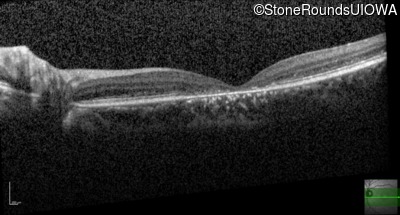

Age at visit: 20 years

Age at visit: 21 years

Age at visit: 23 years

The clinical features favoring the diagnosis of ABCA4-associated autosomal recessive Stargardt disease include: loss of acuity in the second decade, reduction in color discrimination and foveal photoreceptor loss on OCT.